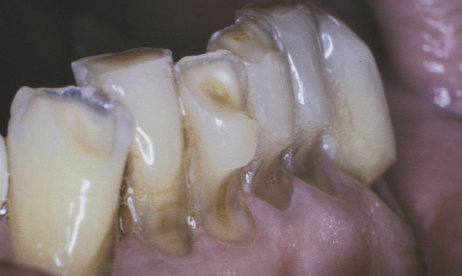

attrition

tooth-abrasive (mechanical)

abrasion

chemical

erosion

occlusal stress

abfraction